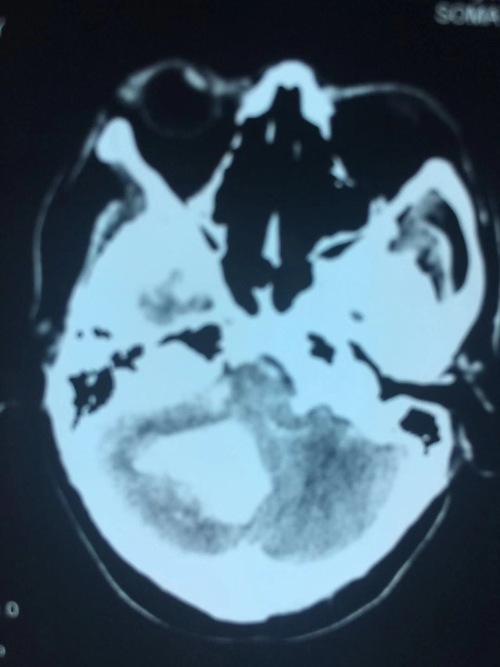

患者蔺某,男,60岁,因“突发剧烈头疼伴恶心呕吐2小时” 入院,经头颅CT检查证实为右侧小脑出血,血肿量约20毫升,血肿达脑干边缘并破入脑室系统。患者既往有高血压病史,入院时血压190/110㎜Hg。结合患者病史、症状、体征及头颅CT检查诊断为高血压性小脑出血。患者入院后病情急剧恶化,意识从清楚迅速转为浅昏迷,必须急诊手术清除小脑血肿。因出血位于小脑,该部位解剖结构复杂,又血肿临近脑干生命中枢,传统开颅手术存在切口大、创伤大、手术时间长等缺点,不利于术后神经功能恢复。而内镜手术损伤小、恢复快,翟德忠主任医师决定为患者施行内镜下小脑血肿清除术。手术在颅骨上仅仅开2厘米左右的骨孔,在内镜辅助下一次清除血肿,手术顺利,手术历时90分钟(比传统手术减少一半)。术后第二天患者意识清楚,四肢活动良好,复查头颅CT血肿清除满意(附图))。